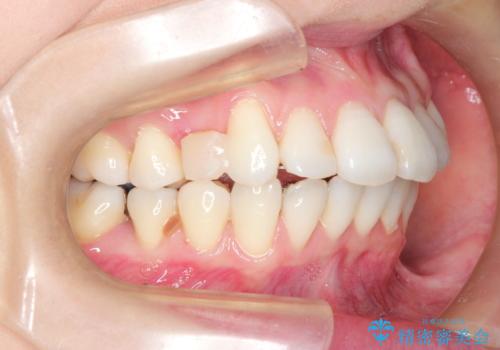

裏側のワイヤー矯正 抜歯して前歯をしっかり後ろに下げる

- 出っ歯が気になるとのことで来院されました。

上顎の、前から4番目の歯を左右1本ずつ抜歯して前歯を後方に下げる計画としました。

目立たずに矯正をご希望でしたので、裏側矯正で治療を行いました。

上下裏側矯正であったため、舌に傷や口内炎ができるなどつらい経験もされましたが、目立たずに治療できたことに喜んでいただけました。